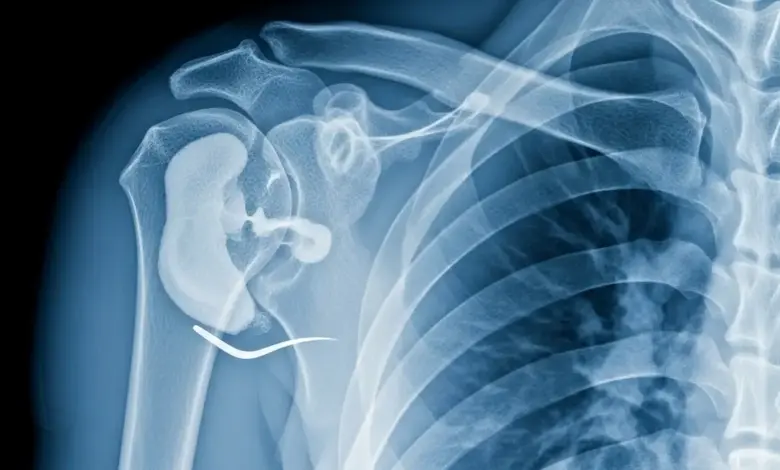

O raio X do ombro costuma mostrar as fases mais adiantadas da doença, com áreas de osso endurecido, afundamento da cabeça do úmero e sinais de artrose.

Quando a suspeita é de osteonecrose ainda no começo, a ressonância magnética é o exame que melhor enxerga o problema. Ela revela alterações dentro do osso antes de qualquer mudança aparecer no raio X.

Em algumas situações, a tomografia do ombro entra como exame complementar, ajudando a definir o quanto a articulação já foi comprometida.

Com base nessas imagens, o médico classifica a doença em estágios, o que orienta a escolha do tratamento conservador ou cirúrgico e ajuda a estimar o risco de progressão.